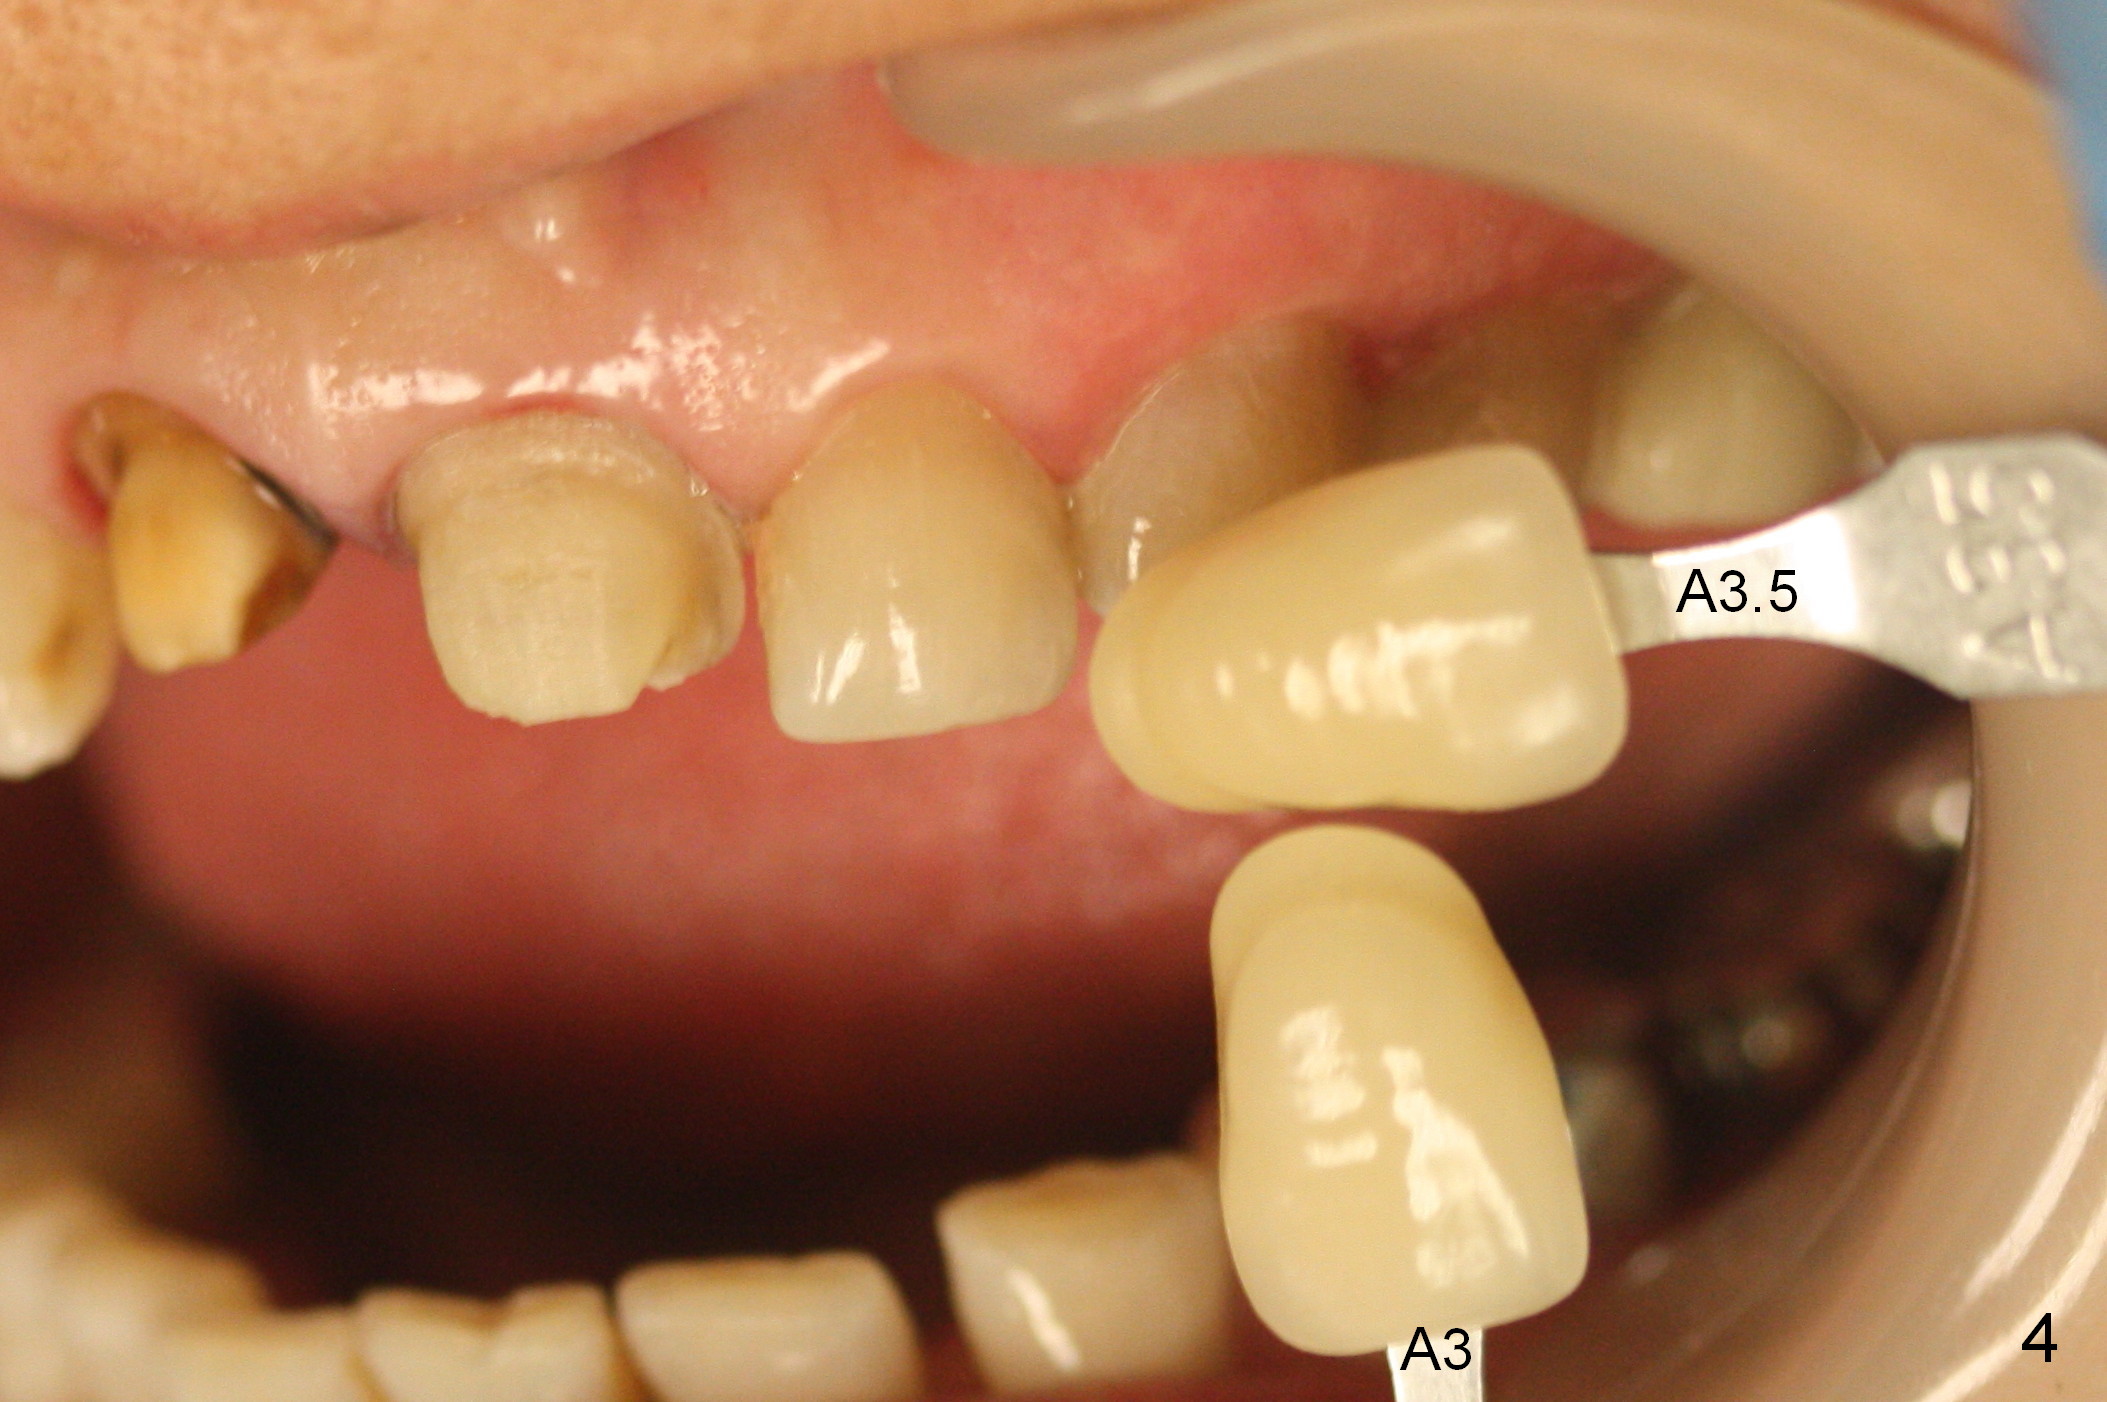

A 54-year-old lady (CL) has a discolored central incisor (#8, Fig.1). Stump shade is shown in Fig.2. Other reference shades are shown in Fig.3-5.